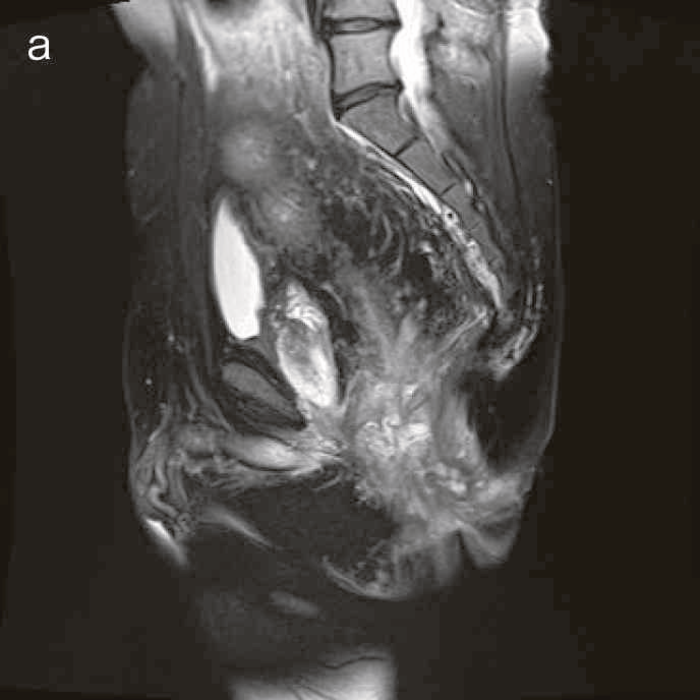

診断時のMRIでは直腸下部壁内から周囲にhigh intensity areaが拡がり,右側には痔瘻の瘻管を認めた。high intensity areaは前方で前立腺や陰茎海綿体付近まで広がっていた。

CTではMRIと同様に広範囲のhigh density areaがあり,癌と炎症が波及した領域の区別がつかず右側方領域にリンパ節腫大を認めた。